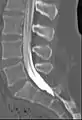

![]() میلوگرافی نشان دهنده ورم عنکبوتیه در مهره های کمری | |

میلوگرافی معمولی در افکنش مورب. غلاف های ریشه عصب در شکل قابل مشاهده اند.